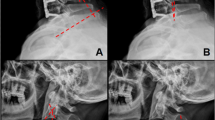

The goal of surgery was to reduce the medullary kyphosis (the bending of the brainstem) over the odontoid, by straightening the CXA [46, 48, 52, 81, 137, 158]. After open reduction of the kyphotic CXA (that is, normalization of the CXA), subjects underwent stabilization and fusion to preserve this corrected relationship (Fig. 2a). Only the subocciput and upper two or three vertebrae were exposed. Suboccipital decompressive craniectomy was not performed. Correction of the CXA was performed by the first author, in the manner similar to that described by Kim, Rekate, Klopfenstein, and Sonntag [81]. The patient was positioned prone in a Mayfield head holder (Fig. 3a). Sensory and motor evoked potentials were monitored throughout the procedure. The reduction was accomplished in one to four iterations, under fluoroscopic guidance, by applying traction to the cranium, posterior translation, and then extension to establish a more normal CXA, with the basion above the midpoint odontoid process (Fig. 3c) [58].

a Preoperative and postoperative CT of a patient showing correction of the CXA and stabilization of the craniocervical junction. b Preoperative and postoperative MRI in the flexed position showing the results of intraoperative correction of the CXA to straighten the neuraxis and thereby reduce the neuraxial strain

Open reduction of the kyphotic CXA. The technique described in Kim et al. (2004) is modified: the head is placed in a Mayfield head holder during exposure; during correction of the CXA, the surgeon breaks from scrub to take hold of the Mayfield head holder; another assistant releases the Mayfield clamps; correction of the CXA is then accomplished by the surgeon who places the head in slight traction (3–5 lbs), extends the head at the craniocervical junction approximately 20°, and posteriorly translates the skull by lifting, to align the basion with the odontoid process (a, b). The assistant then locks the clamps and fluoroscopic imaging is performed to measure the CXA, the position of the basion with respect to the odontoid, the “gaze” angle, and the presence of cervical lordosis (c). The maneuver may require two to four iterations before the final and optimal alignment is confirmed by fluoroscopy

Clivo-axial angle